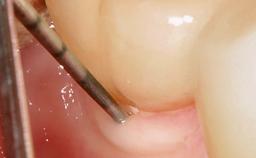

Surgical Management of Peri-Implantitis: Reconstructive Surgical Treatment with Three-Year Follow-up After Treatment

Despite anti-infective surgical treatment, some patients may experience recurrent infection and progressive bone loss requiring additional treatment. Removal of Implant Due to Recurrent Infection describes a conservative approach using an implant retrieval tool without the need for excessive bone removal or use of a trephine.

A 70-year-old female patient was referred by her general dentist to the periodontist for assessment and management of an infection associated with implant 36. The general dentist had noted suppuration on probing during examination.